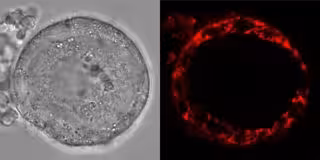

Los óvulos humanos se forman por primera vez en los ovarios durante el desarrollo fetal, pasando por diferentes etapas de maduración. Durante las primeras etapas, los óvulos inmaduros (conocidos como ovocitos) permanecen en un estado de arresto celular, y perduran inactivos hasta 50 años en los ovarios. Como todas las células eucariotas, los ovocitos contienen mitocondrias, las baterías o el motor de la célula, que utilizan para generar energía para sus necesidades durante este período de latencia.

Usando una combinación de imágenes en vivo, técnicas proteómicas y bioquímicas, las autoras del estudio encontraron que las mitocondrias en los ovocitos humanos y de ranas Xenopus usan vías metabólicas alternativas para generar energía nunca antes vistas en otros tipos de células animales.